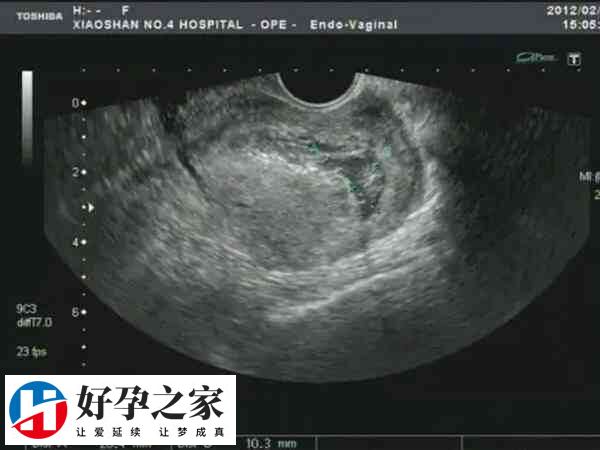

7、定期产前检查,并定期复查B超观察保留胎儿的生长发育情况;

8、在16周妊娠时需行B超检查,注意观察子宫颈发育情况及有无内口松弛,必要时行宫颈环扎术,预防流产与早产发生